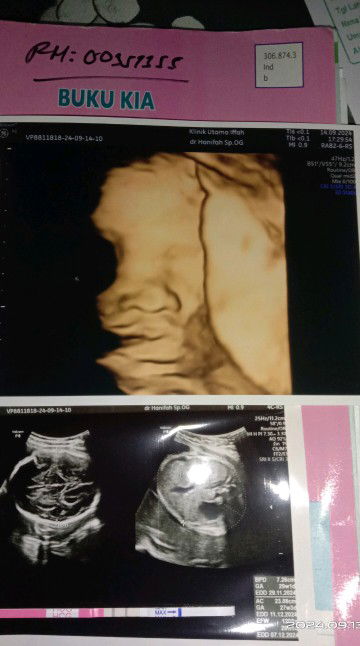

Bund saya bingung , saya di paksa makan telur kampung mentah campur madu sama bumer, sedangkan ibu hamil kan gak boleh makan makanan mentah.. Alesannya biar kuat dan sehat ... Mau pura² gak makan tapi diliatin bumer terus .. mau di makan takut knapa² sama debay nya . Bingung bund😕.. #Sharing_dong_Bund #bantujawab #SeriusTanya